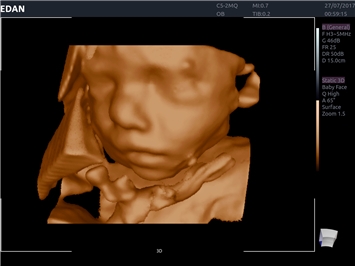

• 3D/4D-визуализация с автоматическим редактированием объема (eFace)

• Акушерства и гинекологии

Режимы акустической прозрачности 3D:

Да

Трехмерная реконструкция ЦДК:

Объемное сканирование:

3D/4D:

Color 3D: